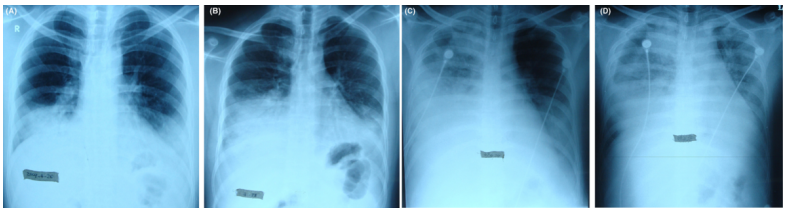

2012年北京朝阳医院的研究对487例社区获得性肺炎(CAP)患者中的18例经实验室确诊的腺病毒重症社区获得性肺炎(SCAP)进行PCR病毒分型,结果均为B型腺病毒,AdV-11、7、3和14型较常见,其中AdV-11型最常见(10/17)。患者临床表现为流感样症状,在发病后6天出现气短或严重呼吸困难。ARDS患者常表现为呼吸困难、血清肌酶升高、影像学双侧多发实变、斑片状或磨玻璃样渗出影。55%应用激素治疗,病死率为11%。其中一例23岁男性因腺病毒引起ARDS,X线胸片显示:发病后第3天双下肺致密片状浸润影(图13A)起病后第5天加重(图13B)起病后第7天右肺及左下肺出现致密实变,左肺上叶尚未明显受累(图13C)第9天双肺广泛实变,呈ARDS改变(图13D)

图片

图13  腺病毒引起的ARDS影像学表现